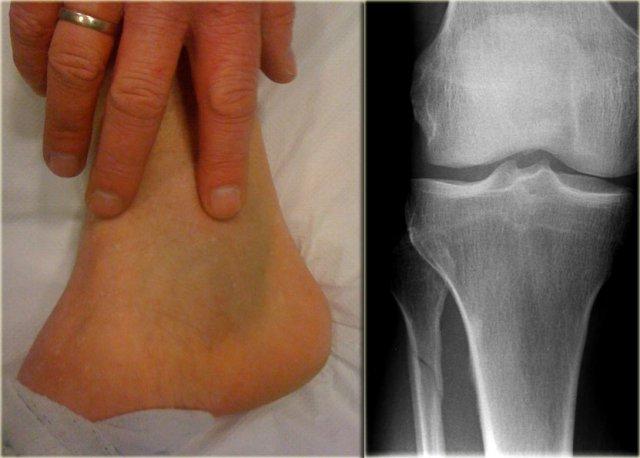

Hình ảnh bên trái của một bệnh nhân có tụ máu ở phía trong cổ chân.

- Nhận định ban đầu

Chúng ta có thể loại trừ gãy xương Weber A hoặc B vì không thấy đường gãy.

Gãy xương Weber C cao vẫn là một khả năng, tức là:- đứt dây chằng bên trong

- gãy xương mác cao

- đứt dây chằng khớp chày mác sau.

- Đánh giá lại

Phim X-quang bổ sung của cẳng chân được chụp thêm và cho thấy gãy xương mác cao, còn được gọi là gãy xương Maisonneuve. - Kết luận cuối cùng

Gãy xương Weber C giai đoạn 4, bao gồm: đứt dây chằng bên trong (dây chằng delta), đứt dây chằng khớp chày mác trước, gãy xương mác cao và có thể đứt dây chằng khớp chày mác sau.

Ca bệnh này minh chứng rằng có thể tồn tại một chấn thương cổ chân không vững cần phẫu thuật ngay cả khi phim X-quang cổ chân không cho thấy gãy xương.